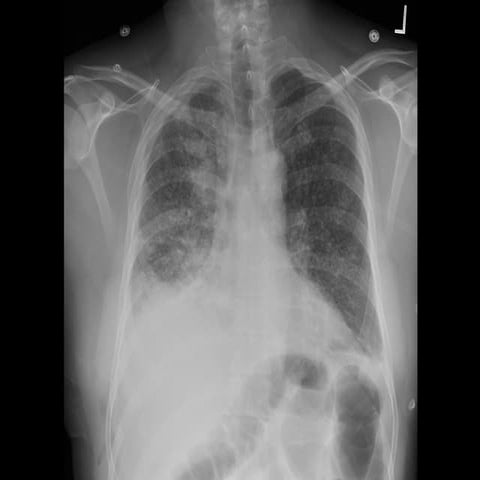

40 year old